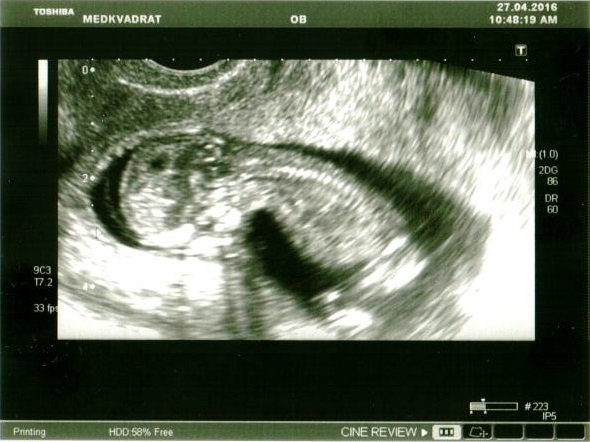

1-й скрининг и УЗИ. 11 нед. 4 дня

27.04.2016

Поздравляю!))) хороший малыш)) шейка у вас и правда отличная, 42мм это и есть размер шейки))